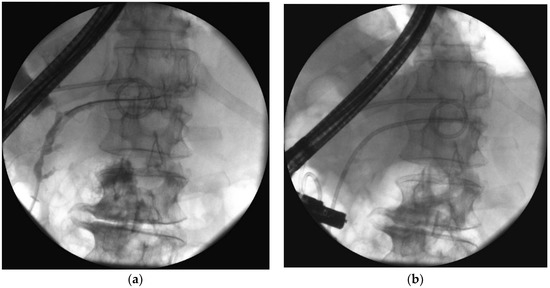

- Smoczyński, M.; Jagielski, M.; Jabłońska, A.; Adrych, K. Endoscopic necrosectomy under fluoroscopic guidance- a single center experience. Wideochir. Inne. Tech. Maloinwazyjne. 2015, 10, 237–243. [Google Scholar] [CrossRef] [PubMed]

- Jagielski, M.; Smoczyński, M.; Studniarek, M.; Adrych, K. Description of Minimally Invasive Methods of Treatment Of Walled-Off Pancreatic Necrosis (WOPN)—The Use Of “Step-Up Approach” In Patient With Pancreatic Necrosis. Pol. Przegl. Chir. 2015, 87, 409–412. [Google Scholar] [CrossRef] [PubMed]